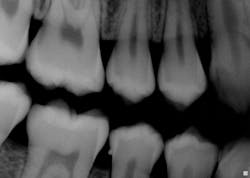

Radiographs/distinguishing characteristics: Radiographically, the enamel pearl is observed as a smooth, radiopaque structure on the root of a multirooted tooth. Since the nodule is below the tissue, it is not noted during the usual oral tissue exam. Enamel pearls are comprised of combinations of pure enamel and sometimes dentin. The dentin core may be found within the nodular entity and it is not uncommon to also detect a pulp horn as well. Pulp vitality testing is needed (see Figures 2, 3).

Figure 2: Courtesy of Dr. Harvey P. Kessler, Baylor College of Dentistry, Texas A & M Health Science Center, Dallas, Texas.

Figure 3: Courtesy of Dr. Harvey P. Kessler, Baylor College of Dentistry, Texas A & M Health Science Center, Dallas, Texas.